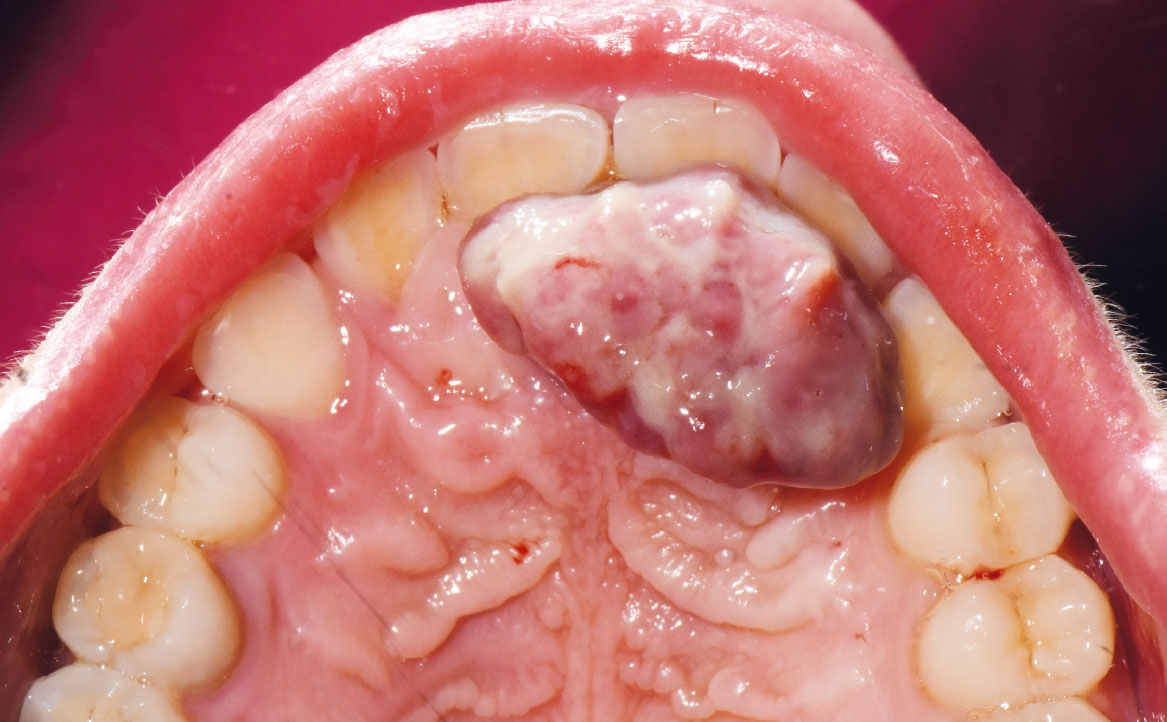

Una donna di 27 anni si è recata presso il Dipartimento di Odontoiatria e Protesi Dentaria dell’Ospedale IRCCS San Raffaele di Milano, diretto dal professor E. F. Gherlone, a causa di una lesione presente sul palato. La paziente, in prima istanza, in seguito a un questionario anamnestico, dichiara di essere al terzo trimestre di gravidanza. Successivamente, all’esame intra-orale è stata riscontrata la presenza di una lesione sessile a livello del palato, osservabile in figura 1 e 2. La diagnosi presuntiva è quella di granuloma piogenico, da confermare attraverso l’esame istopatologico.

La lesione di circa 2 cm, fissata in formalina al 10% tamponata, è stata inviata al reparto di Istologia e Anatomia Patologica dell’IRCCS Ospedale San Raffaele al fine di eseguire l’analisi istopatologica.